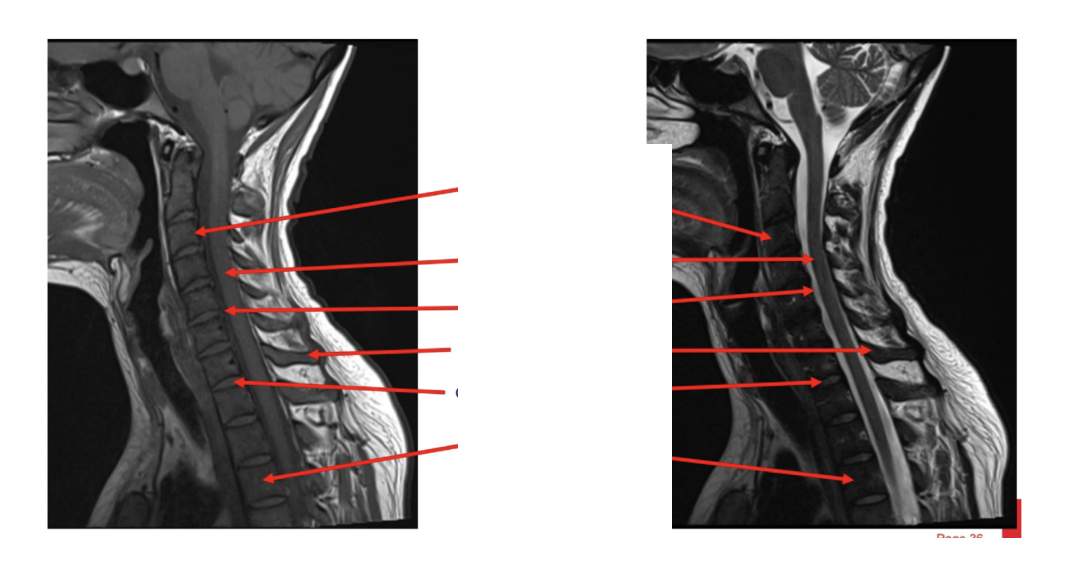

Sequences + Pathology

• T2, T2FS, T1C+

• Path = multiple sclerosis

• Increased signal within the spinal cord confirming the presence of lesions